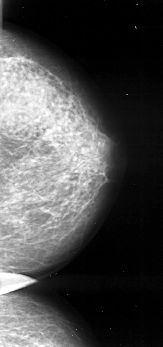

A_1026_1.LEFT_MLO

LEFT_MLO LINES 6271 PIXELS_PER_LINE 2851 BITS_PER_PIXEL 16 RESOLUTION 42 OVERLAY